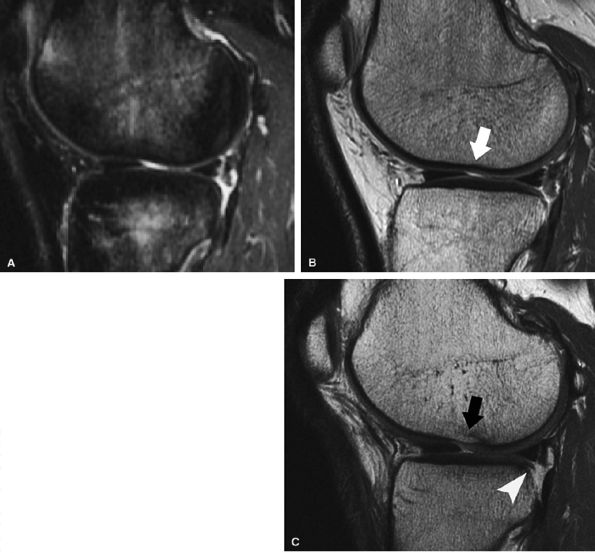

FIGURE 7.6 ● (A) Sagittal fat-suppressed T1-weighted gradient-echo MR image sequence of the knee demonstrates a focal high-grade partial-thickness cartilage defect overlying the medial femoral condyle (arrowheads). In the equivalent time required to acquire this single pulse sequence, cartilage-sensitive fast spin-echo MR sequences in two planes—sagittal (B) and coronal (C)—can be obtained, in which the depth of the lesion is much better delineated. (Reprinted by permission of SAGE Publications, Inc., from Am J Sports Med, in press.)

FIGURE 7.18 ● Prospective MR evaluation of a bone bruise in the knee of a 28-year-old man with a complete ACL tear. Sagittal fat-suppressed (A) and fast spin-echo (B) MR images obtained at the time of injury demonstrate characteristic bone marrow edema with compression of cartilage over the lateral femoral condyle (white arrow). A sagittal MR image obtained 19 months later (C) demonstrates proud subchondral bone with focal cartilage loss over the condyle (black arrow), as well as flap formation over the tibial plateau (arrowhead). (Reprinted by permission of SAGE Publications, Inc., from Am J Sports Med, in press.)